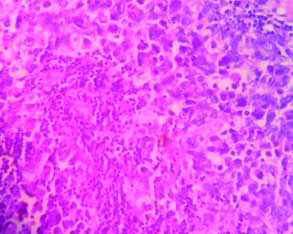

Microscopy showed breast parenchyma with a neoplasm arranged in sheets, lobules, nests and alveolar pattern [Table/Fig-2,3]. The tumour cells are small round with scant cytoplasm, round vesicular nucleus separated by fibrous septa seen infiltrating into the adjacent fatty tissue [Table/Fig-2,3]. Stroma showed lymphocytic infiltrate. The NAC, superior, inferior margin showed tumour infiltration. Rest of the margins and posterior margin were free. Five out of 11 nodes showed metastatic deposits with similar morphology [Table/Fig-4]. With this histology, we came to the conclusion of possibilities of small round cell tumour of breast.

Node shows metastatic deposits (H&E, 40x view).